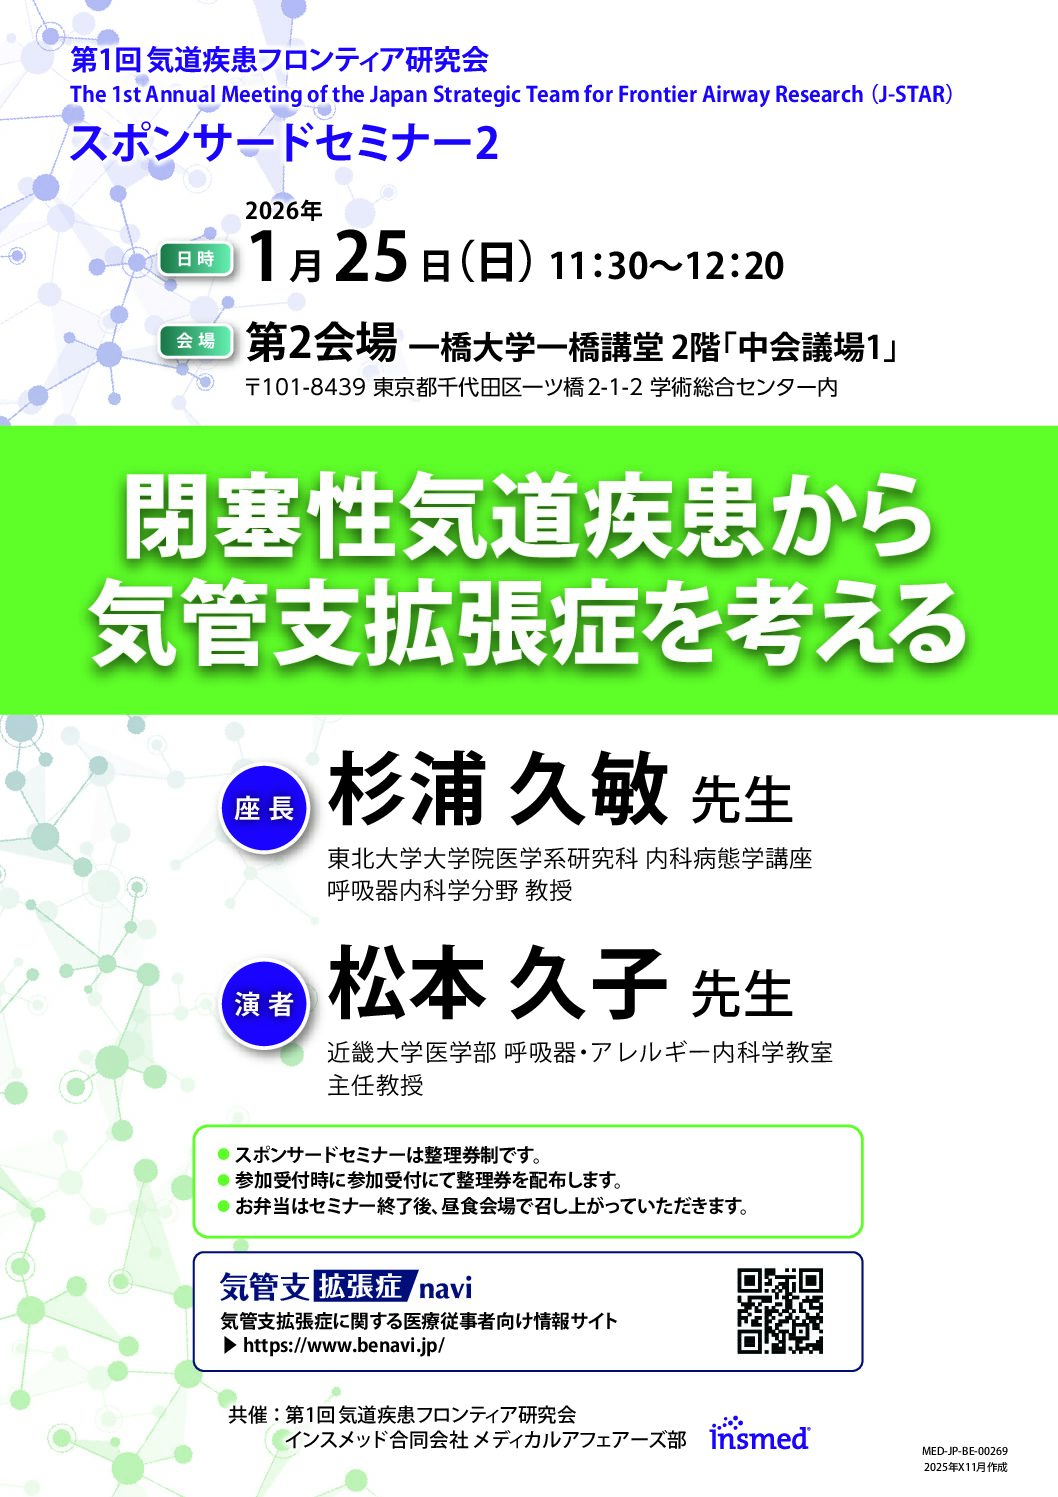

学会共催セミナー

第1回気道疾患フロンティア研究会スポンサードセミナー2閉塞性気道疾患から気管支拡張症を考える会場:第2会場 一橋大学一橋講堂 2階「中会議場1」

開催日時2026年1月25日(日)11:30~12:20

座長:杉浦 久敏先生

東北大学大学院医学系研究科 内科病態学講座

呼吸器内科学分野 教授

演者:松本 久子先生

近畿大学医学部 呼吸器・アレルギー内科学教室

主任教授